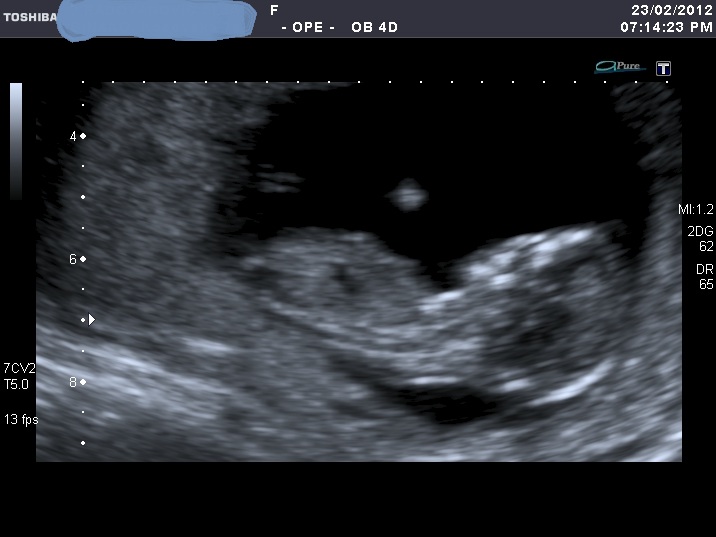

I'm sorry for spaming again with my nub shots, but now when I look at u/s pics I'm not sure I can a see a nub at all????

If you can see it, please enlighten me where to look. Also I think scull looks girly on some pics and boyish on the others.

I was 12 weeks, measuring 12 weeks 5 days